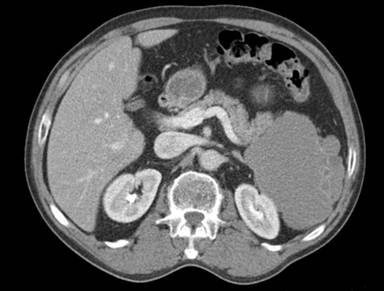

The patient is a 62-year-old male who presented to a rural clinic with complains of vague left-sided abdominal pain. A Computed tomography (CT) scan was obtained which showed a left-sided retroperitoneal mass with a possible cystic component (Figure 1). Resection of the mass was advised and the patient was transferred to our tertiary academic medical center. Abdominal surgical exploration revealed a large mass containing a cystic cavity (4.8x3.7x1.9 cm in aggregate) consisting of hemorrhagic fatty soft tissue and purulent appearing debris originating from the tail of the pancreas. The cyst was removed and sent for pathologic examination. Microscopy revealed multiple epidermoid cysts within accessory splenic tissue (Figure 2). The cysts were lined by stratified squamous epithelium, some of which was keratinizing, and were variable in size. Several cysts appeared to have ruptured and had surrounding fat necrosis and foreign body giant cells. The lining of the cysts was positive for CEA on immunohistochemistry. The findings are consistent with a benign epidermoid cyst arising within accessory splenic tissue in the tail of the pancreas. The patient recovered without complication.

Figure 1. Computed tomography (CT) scan demonstrating a large, left-sided cystic mass near the tail of the pancreas. |